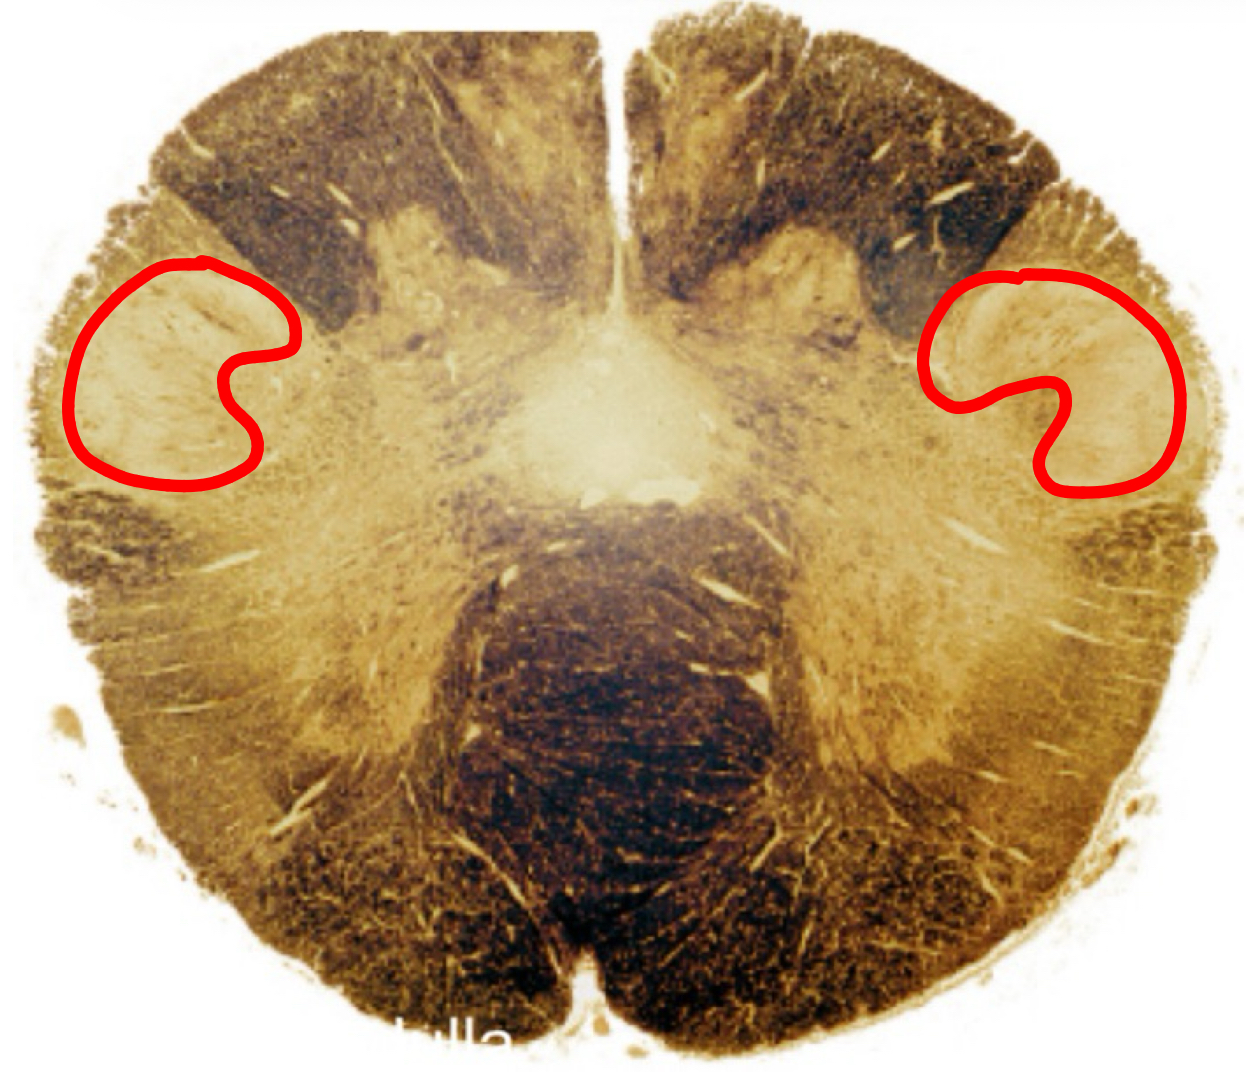

inferior olivary complex rostral medulla